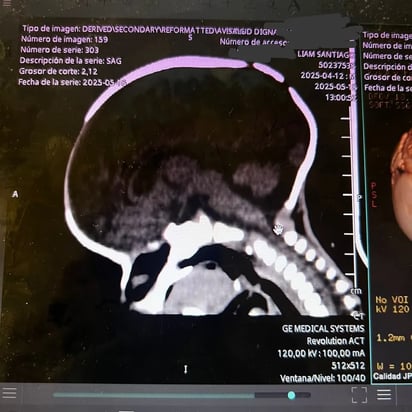

Santi, como lo llaman de cariño, tiene apenas un mes de nacido, sin embargo, tras una revisión médica se le diagnosticó un problema en su cabeza.

De acuerdo a lo que contó su familia, se trata de una craneosinostosis, una condición en la que las suturas del cráneo del bebé se cierran prematuramente, impidiendo su crecimiento de manera normal.

Esto puede generar varios problemas, que no le permiten a Santi desarrollarse como un bebé de su edad, por ello es necesario operarlo lo antes posible.